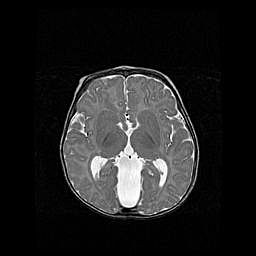

Множественные кисты обоих полушарий головного мозга, наибольшая из них в правой затылочной области. Ассиметричная атрофическая гидроцефалия.

Возраст: 7 месяцев

Вес: 5660 г

Пол: мужской

Окружность головы: 41,5 см

Срок гестации: 28-29 недель

Кисты головного мозга развиваются в результате многоочаговых некрозов вещества мозга и возникают вследствие перенесенной перинатальной инфекции, менингитов, энцефалитов, асфиксии, родовой травмы, расстройств мозгового кровообращения различного генеза. Образованию кист в веществе головного мозга плодов и новорожденных способствуют такие факторы, как высокое содержание в нем воды, недостаточная (или отсутствие) миелинизация и слабая астроглиальная реакция на повреждение.

Кисты могут сочетаться с гидроцефалией и другими поражениями головного мозга.